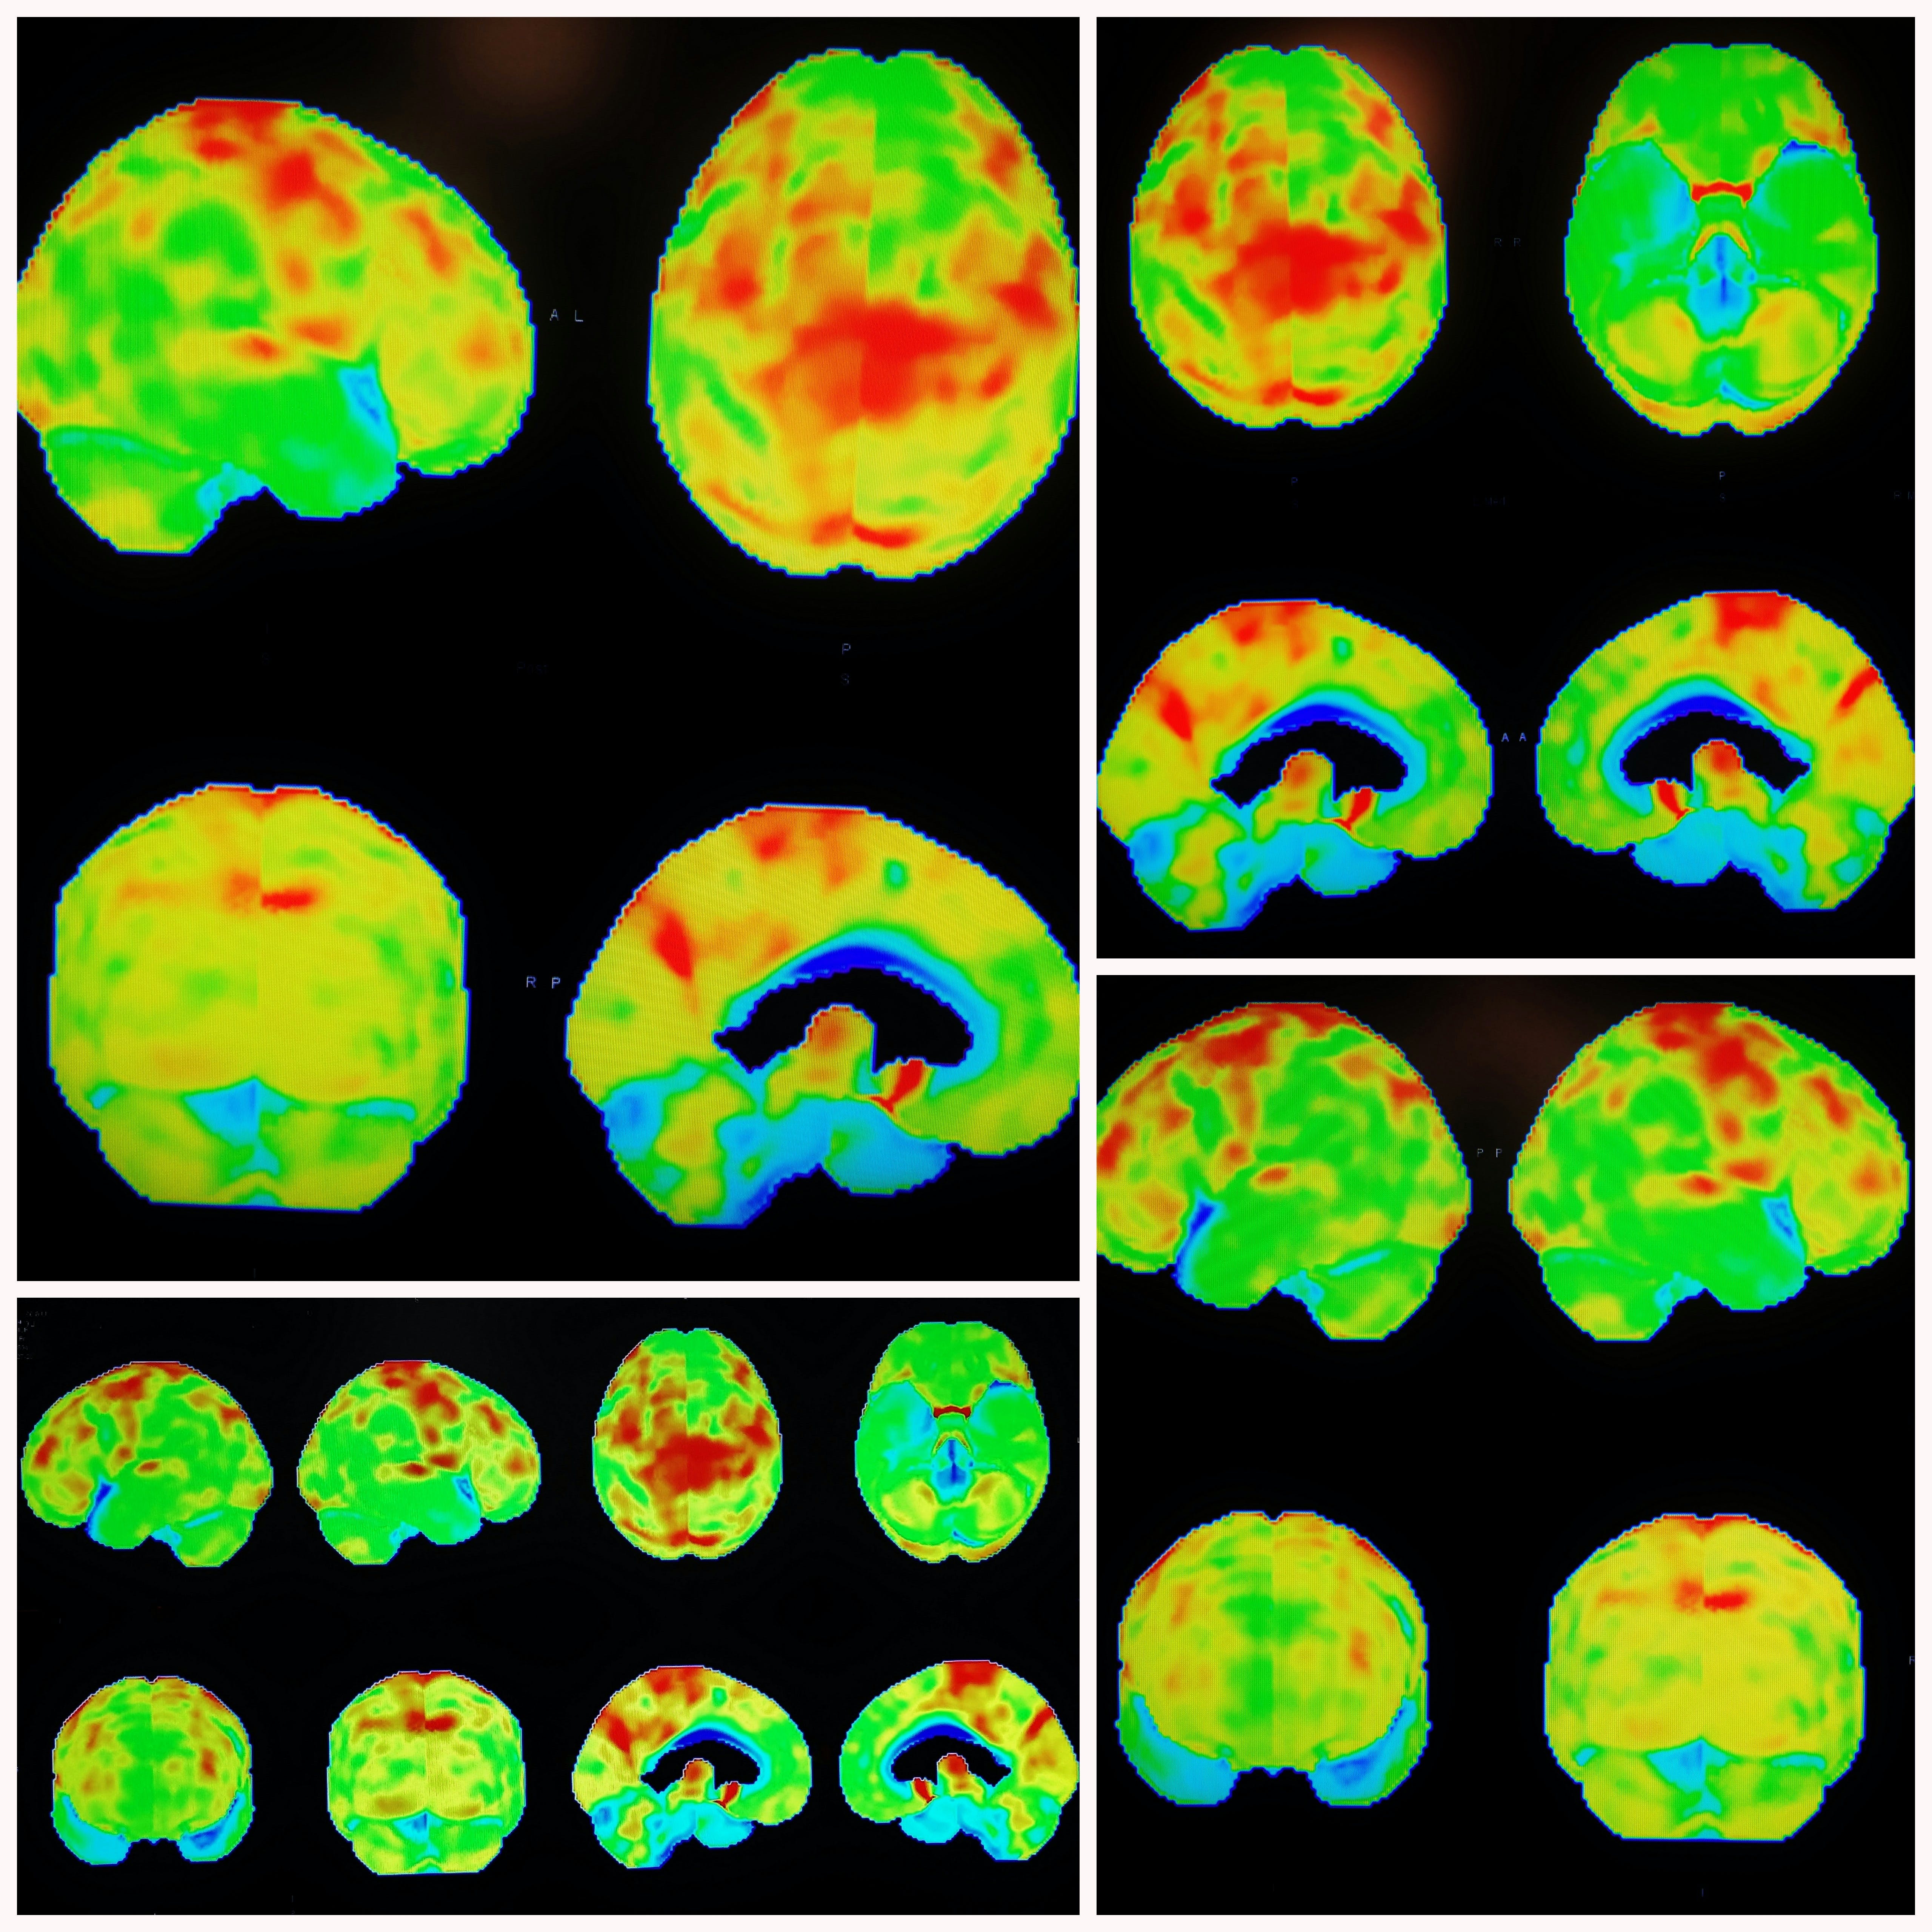

In 34 people with Parkinson’s disease risk factors, researchers conducted PET scans of the heart to gain insight into levels of the neurotransmitter norepinephrine. They found that the scans could distinguish individuals who would later be diagnosed with Parkinson’s or Lewy body dementia—both are brain diseases caused by abnormal deposits of the protein alpha-synuclein that form clumps known as Lewy bodies. The research was conducted at the NIH Clinical Center, currently the only location for 18F-dopamine PET scanning.

In the present study, the research team led by David S. Goldstein, M.D., Ph.D., NINDS Principal Investigator, found that at-risk individuals with low 18F-dopamine-derived radioactivity in the heart were highly likely to develop Parkinson’s or Lewy body dementia during long-term follow-up, compared to individuals with the same risk factors but with normal radioactivity. PET scans work by using a radioactive tracer to visualize metabolic or biochemical processes in body organs.